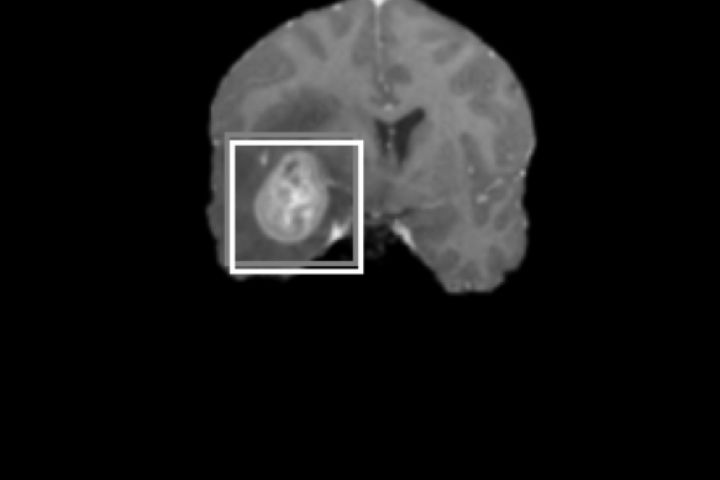

Используя Pytorch, Pillow, Sklearn была создана и обучена модель нейронной сети со сверточными слоями. Для увеличения количества входных даных, изображения были аугментированы.

Модель на тестовом наборе показала индекс Жаккарда 0.78.